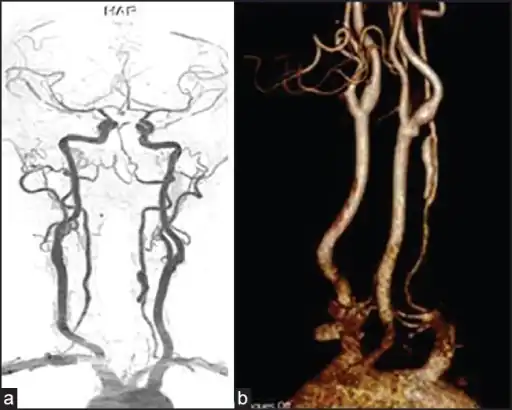

Vertebral artery dissection with focal dilatation of involved segment -

Magnetic resonance angiogram of the neck vessels in a person with Ehlers-Danlos syndrome type IV; it shows a dissection of the left internal carotid artery, dissection of both vertebral arteries in their V1 and V2 segments and a dissection of the middle and distal third of the right subclavian artery. Such striking episodes of dissection are typical for this "vascular" subtype of Ehlers-Danlos syndrome. -

A reconstruction of the vertebral arteries from a CT scan, seen from the front. From the bottom, V1 is from the subclavian artery to the foramina, V2 is from the foramina to the second vertebra, V3 is between the foramina until entry into the skull, and V4 is inside the skull embedded in the dura mater. They merge into the basilar artery, which then divides into the posterior cerebral artery.